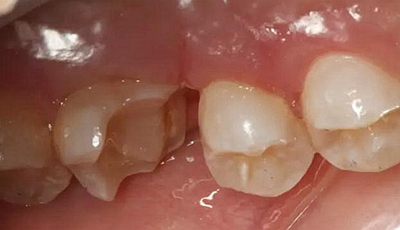

一周后拆除縫線,試戴高嵌體,試戴合適后雙固化粘結。調(diào)合,拋光。